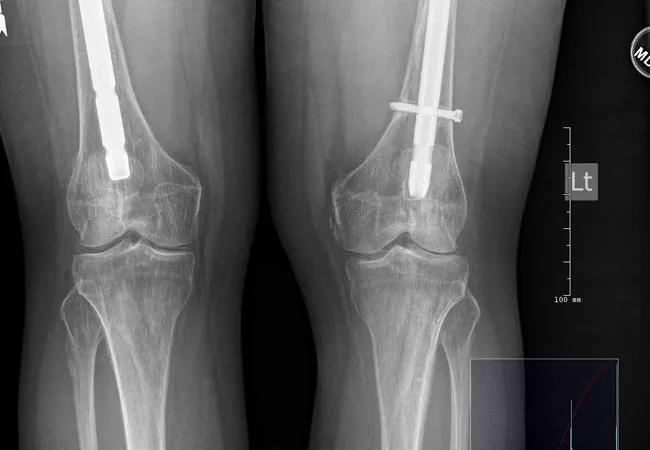

Late, Severe Effects of Hypophosphatasia

A case study from Chad Deal, MD, illustrates how patients may present

Rheumatologists most commonly see the adult form of hypophosphatasia (HPP), one of six major forms of the disease. The adult form is characterized by muscle pain, muscle weakness, recurring stress fractures, osteomalacia, a history of dental abnormalities and calcium pyrophosphate dihydrate crystal deposition in the cartilage (CPPD). Only a few small cohort studies characterize adult HPP in terms of clinical, radiographic and laboratory presentation.

Clinicians should take notice of persistent hypophosphatasemia, consider the diagnosis of HPP and be cautious when considering potent antiremodeling therapy in these adults since the underlying disorder is a defect in mineralization (osteomalacia), not osteoporosis.

• Delayed or incomplete fracture healing or fracture nonunion.

• Repeated episodes of orthopedic surgery for complications of HPP, especially for nonunion and delayed union fractures.